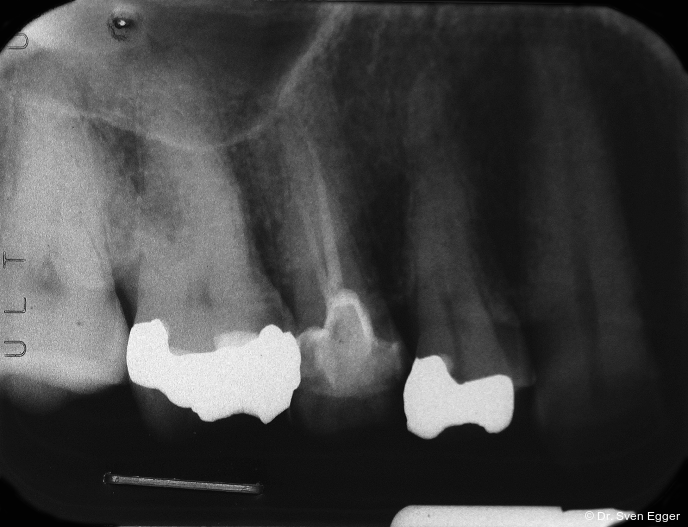

Das OPG zeigt insuffiziente endodontische Versorgungen an 15, 25 und 46. Die Kieferhöhle rechts zeigt eine kirschgroße, kugelige Verschattung (Überweisung/Abklärung Kieferchirurgie).

- Sinusitis maxillaris rechts (Verdacht auf Mukozele)

- Revision der insuffizienten Wurzelfüllungen 15, 25 und 46. Bei Nichterfolg jeweils Extraktion, Ersatz durch Einzelzahnimplantat nach Abheilphase von zwei Monaten.